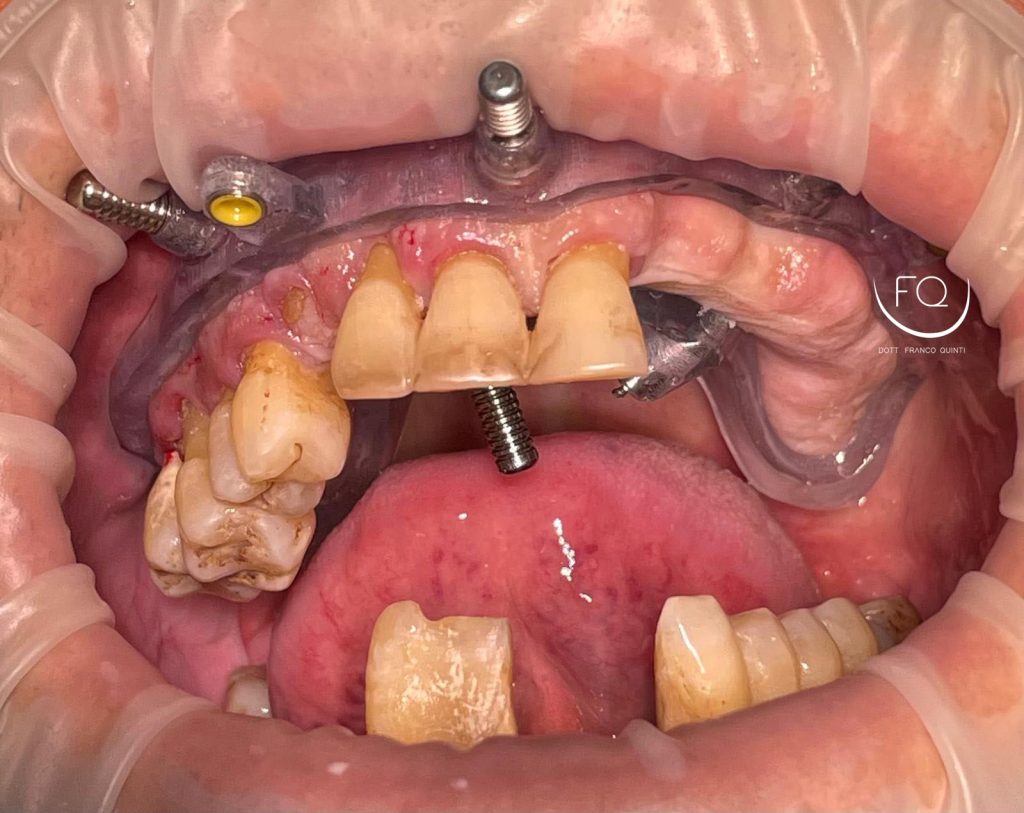

Questa settimana vi presento un caso di chirurgia computer guidata dell’arcata superiore realizzato con dime scomponibili con esecuzione contestuale di un carico immediato.

Nelle prossime settimane vi mostrerò dei brevi video di questo caso relativi alla scomposizione e alla progettazione delle dime chirurgiche.